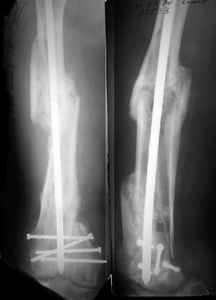

A new toy is more interesting and fashionable. And anyway it is not panacea, i have already seen presentations with LISS failures like the attached one presented by D.Seligson. And people also demonstrated incisions say that the method is not so LESS invasive as it supposed to be.